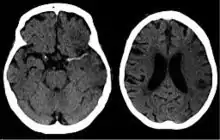

![]() تصوير مقطعي محوسب للدماغ يظهر سكتة دماغية في نصف الكرة الدماغية الأيمن نتيجة نقص التروية. تصوير مقطعي محوسب للدماغ يظهر سكتة دماغية في نصف الكرة الدماغية الأيمن نتيجة نقص التروية. | |